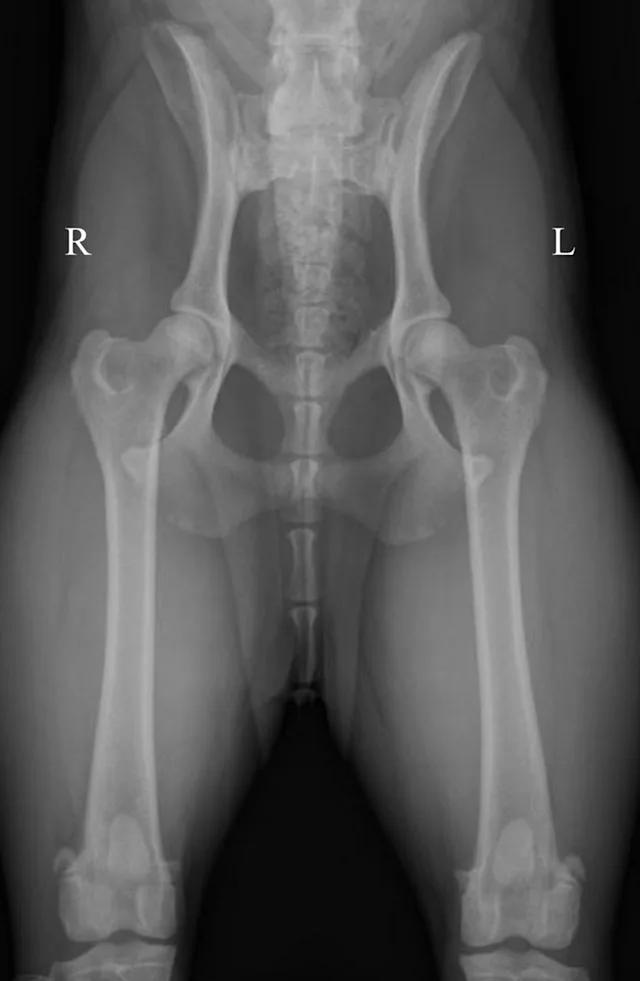

Pelvic radiographs must be assessed for adequate positioning and should be repeated if the pelvis is oblique, as in Figure 2A. In this example, there are multiple positioning errors. The right femur/stifle should be further internally rotated (so the patella is more centrally located over the femur). The right stifle should be moved axially (medially) so the femurs are parallel. The pelvis is rotated with the right hemipelvis farther away from the imaging plate. In Figure 2B, the right hemipelvis has been elevated from the imaging plate. In this image, the right (up) obturator foramen is increased in width compared with the left. Additionally, the left (down) ilium appears narrower.

Oblique positioning will result in false assessment of dorsal acetabular rim coverage of the femoral head, as shown in Figure 2C. The dorsal acetabular rim (white arrows) appears to provide more coverage of the right femoral head and less coverage on the left side. When the patient is properly positioned, as in Figure 2D, it is evident that coverage of the dorsal acetabular rim (white arrows) is similar on both sides.